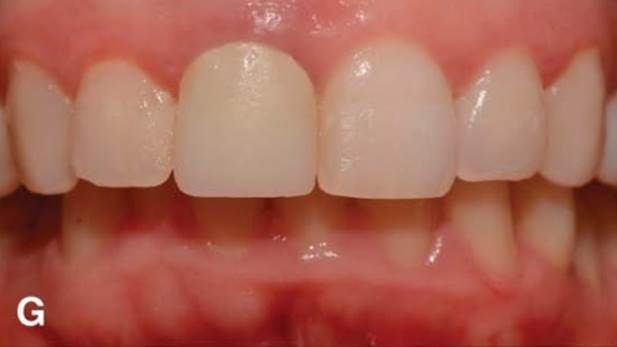

Clinical case: Immediate post-extraction insertion of implant & immediate loading

- Courtesy of Prof. Giuseppe Luongo, Italy -

AnyRidge, immediate loading, single implant, multicenter study, maxillary anterior, Prof. Giuseppe Luongo, single replacement

AnyRidge implant system

Immediate functional loading of single implants: a multicenter study with 4 years of follow-up

/J Dent Res Dent Clin Dent Prospect 2018; 12(1):26-37 | doi: 10.15171/joddd.2018.005

https://www.ncbi.nlm.nih.gov/pubmed/29732018